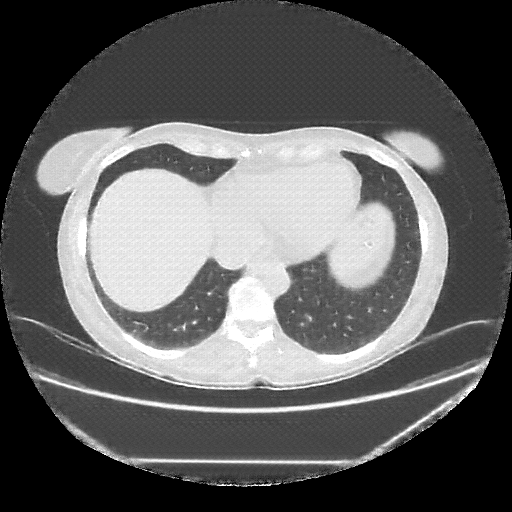

Reconstructed NATIVE CT scan (cycle consistency)

Full window (WL 1023.5, WW 4095 β†’ Low βˆ’1024, High +3071)

Lung window (WL -600, WW 1500 β†’ Low βˆ’1350, High +150)

Mediastinum window (WL 40, WW 400 β†’ Low βˆ’160, High +240)